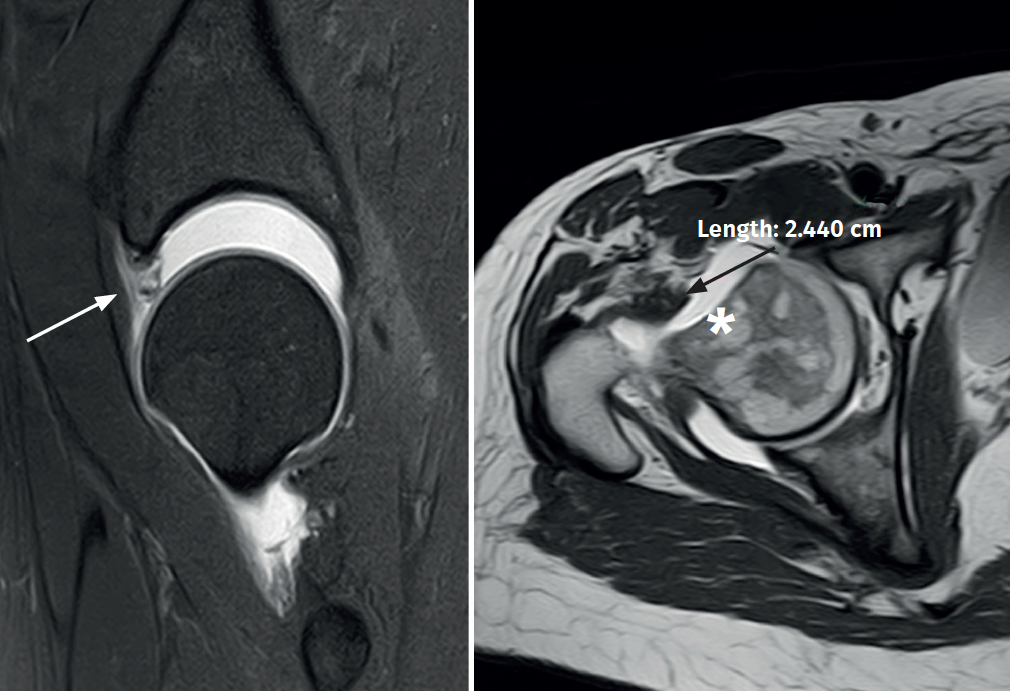

A 38-year-old woman subjected to surgery three years ago due to right femoroacetabular impingement presented with residual pain. At exploration, the Faber and impingement maneuvers were very positive, as was the dial test. Anterior instability maneuvering (abduction and extension) with apprehension during gentle external rotation maneuvers also proved positive. No rotational anomalies were evidenced at exploration. The modified Harris score was 68 points. Radiographically, the head-neck junction was correct, in the same way as acetabular coverage. On the other hand, joint magnetic resonance imaging showed areas of 11-3 o'clock acetabular chondrolabral degeneration / re-rupture and a deficient joint capsule corresponding to type 3 of the Aoki classification(5)(Figure 1), with no version structural alterations of the acetabulum and femur. In addition, important joint distraction displacement with gentle traction was observed. Postsurgical hip microinstability due to mixed capsular and labral joint sealing loss was diagnosed. In view of these findings, simultaneous arthroscopic labral and capsular reconstruction was proposed.

With regard to the types of iatrogenic capsule defects following hip arthroscopy, the group of Aoki(5) published a very useful classification for deciding their treatment, based on the joint magnetic resonance imaging findings: grade 0 (normal capsule volume and anatomy); grade 1 (increased capsule volume and redundancy, but with the anterior capsule continuous and intact); grade 2 (intact capsule continuity but with irregular thickness and focal tearing or alterations); and grade 3 (highly irregular capsule contour and important fluid extravasation through the defect). Direct repair techniques usually suffice in grade 1 and 2 defects, though in grade 3 defects the risk of failure following such repair is high; in these situations it is therefore advisable to consider capsular reconstruction techniques(8).